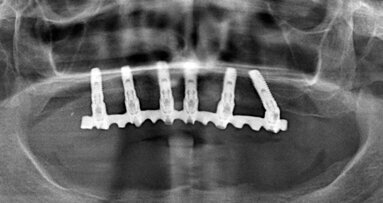

Per le protesi full-arch si raccomanda un’occlusione bilaterale bilanciata nel caso di antagonista protesico e funzione di gruppo con una lieve guida anteriore nel caso di antagonista con denti naturali, senza differenza fra superiore e inferiore. Nella protesi a carico immediato i contatti bilaterali saranno simultanei e puntiformi su tutti i denti, mentre nella definitiva i contatti saranno sfioranti sugli incisivi. In lateralità si avranno tragitti lineari nella funzione di gruppo o una guida canina, ma è preferibile una guida canina. In protrusiva si avranno tragitti lineari a carico degli incisivi e nel carico immediato anche a carico dei canini. Evitare i contatti bilancianti nel carico immediato e ricercare uno o più contatti bilancianti nei movimenti escursivi della protesi definitiva. È importante minimizzare al massimo i cantilever e lasciarli sotto-occlusi sulla protesi a carico immediato, e comunque lasciare sotto-occluso il cantilever sull’ultimo dente della protesi definitiva.

Fig. 1_Protesi a carico immediato con contatti bilaterali simultanei e puntiformi su tutti i denti.